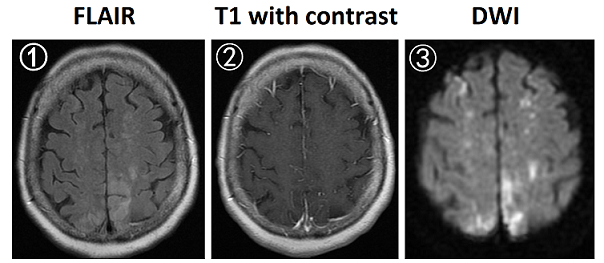

【113-2 醫學(四) 第45題】70歲女性為肺癌病人,因右腳無力就診,抽血檢查發現D-dimer檢驗數值為16 mg/L(正常值為<0.5 mg/L),腦部磁振造影(MRI)檢查結果如下圖(①fluid–attenuated inversion recovery [FLAIR];② 施打顯影劑之T1影像;③diffusion–weighted imaging [DWI])。下列何者最可能是腦部病灶的原因?